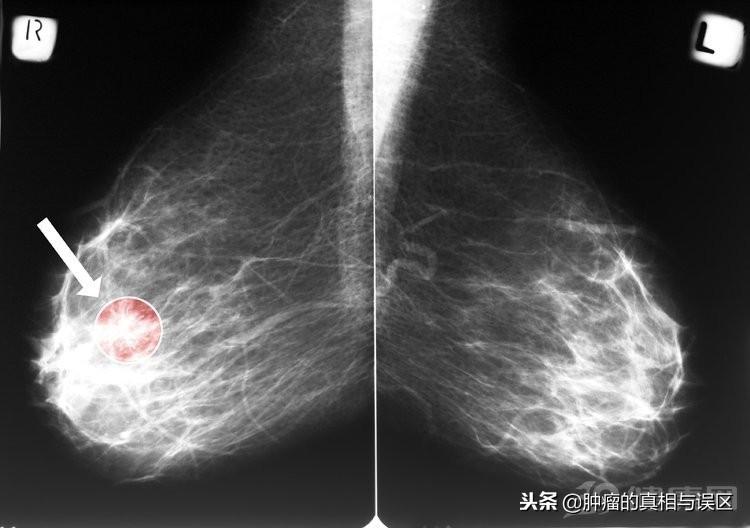

乳腺癌的早期图片 乳腺癌的症状的照片

1、乳房肿块

乳房出现肿块是乳腺癌一个很典型的早期症状,大多数的乳腺癌早期都是无痛性的肿块,少数的女性会伴随着隐痛或者是刺痛。对于成年女性来说,当乳房内出现不知名的肿块的时候,一定要引起足够的重视,一般情况下,乳腺癌所出现的肿块都是单个的,只有少部分的女性会出现过个的肿块。